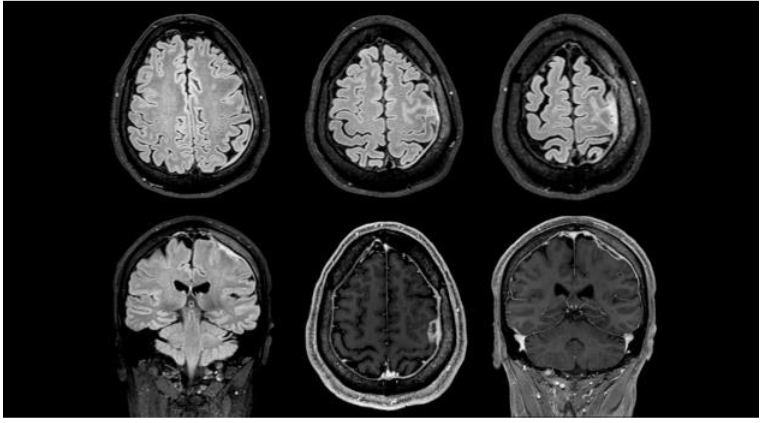

Five days later, the patient returned with worsening headaches and right-sided myoclonus with secondary generalised seizures. Neurological examination revealed no focal deficits. EEG was normal. CSF analysis showed mild pleocytosis (5 white blood cells), elevated protein (1.13 g/L), normal glucose, and negative cultures including 16S rRNA PCR. Brain MRI demonstrated focal frontoparietal pachymeningitis with gadolinium enhancement.

A diagnosis of melioidosis with CNS involvement was established. Treatment with intravenous meropenem (6 g/day) was initiated for three weeks, followed by oral trimethoprim-sulfamethoxazole (TMP-SMX) for 10 weeks. The patient’s symptoms resolved completely. Follow-up MRI at three months showed resolution of pachymeningeal enhancement.